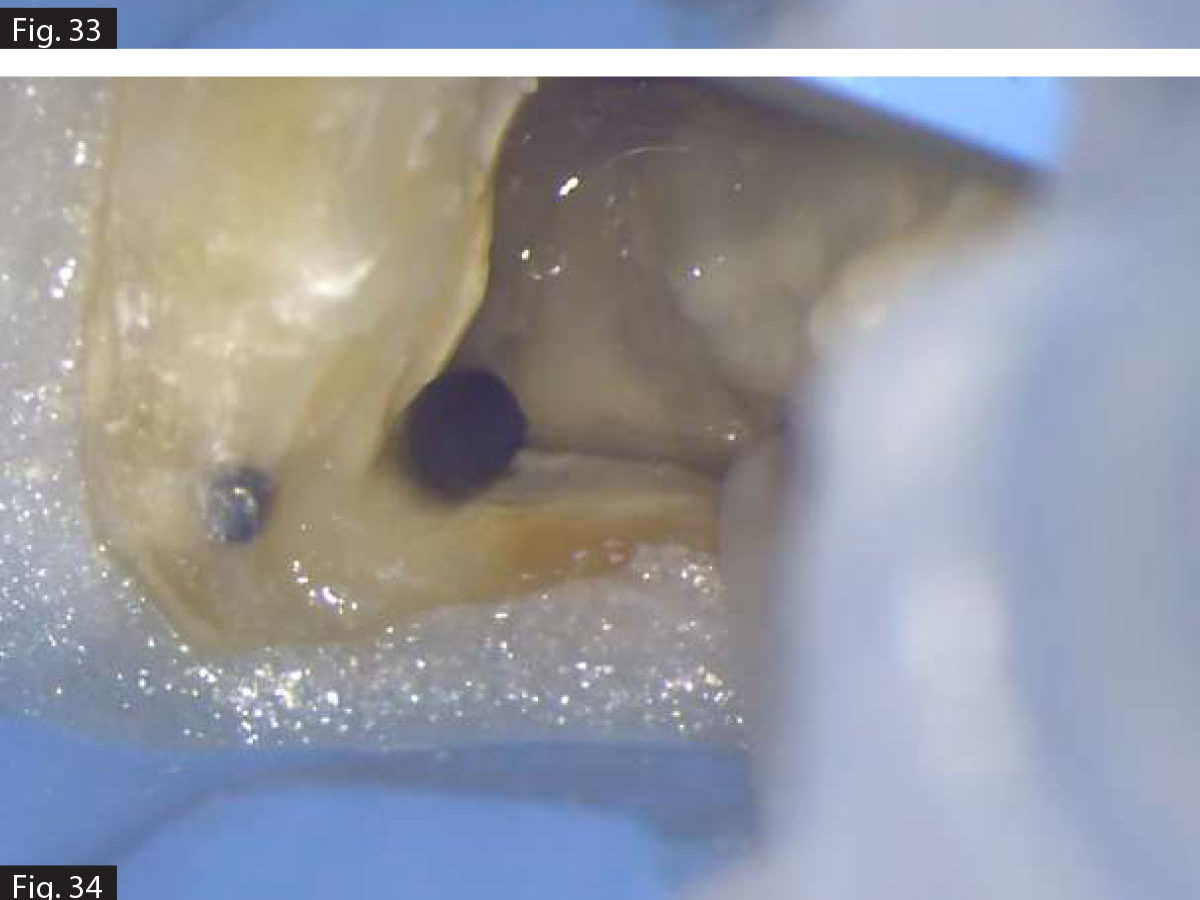

1. Enhanced Debris Removal – Mechanical instrumentation alone cannot fully clean the intricate anatomy of the root canal system. Irrigation solutions help clean out dentin debris, pulp tissue, and bacteria from areas that instruments cannot reach.

3. Dissolution of Organic and Inorganic Matter – Some solutions can break down necrotic tissue and smear layers, improving the penetration of medicaments and sealers.

New technologies, such as ultrasonic activation, negative pressure irrigation, and dynamic agitation systems, enhance the effectiveness of irrigants by improving penetration and ensuring thorough disinfection of the complex root canal anatomy.